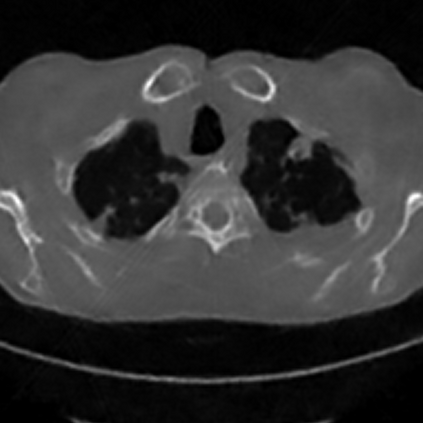

Sparse-view computed tomography (CT) -- using a small number of projections for tomographic reconstruction -- enables much lower radiation dose to patients and accelerated data acquisition. The reconstructed images, however, suffer from strong artifacts, greatly limiting their diagnostic value. Current trends for sparse-view CT turn to the raw data for better information recovery. The resultant dual-domain methods, nonetheless, suffer from secondary artifacts, especially in ultra-sparse view scenarios, and their generalization to other scanners/protocols is greatly limited. A crucial question arises: have the image post-processing methods reached the limit? Our answer is not yet. In this paper, we stick to image post-processing methods due to great flexibility and propose global representation (GloRe) distillation framework for sparse-view CT, termed GloReDi. First, we propose to learn GloRe with Fourier convolution, so each element in GloRe has an image-wide receptive field. Second, unlike methods that only use the full-view images for supervision, we propose to distill GloRe from intermediate-view reconstructed images that are readily available but not explored in previous literature. The success of GloRe distillation is attributed to two key components: representation directional distillation to align the GloRe directions, and band-pass-specific contrastive distillation to gain clinically important details. Extensive experiments demonstrate the superiority of the proposed GloReDi over the state-of-the-art methods, including dual-domain ones. The source code is available at https://github.com/longzilicart/GloReDi.